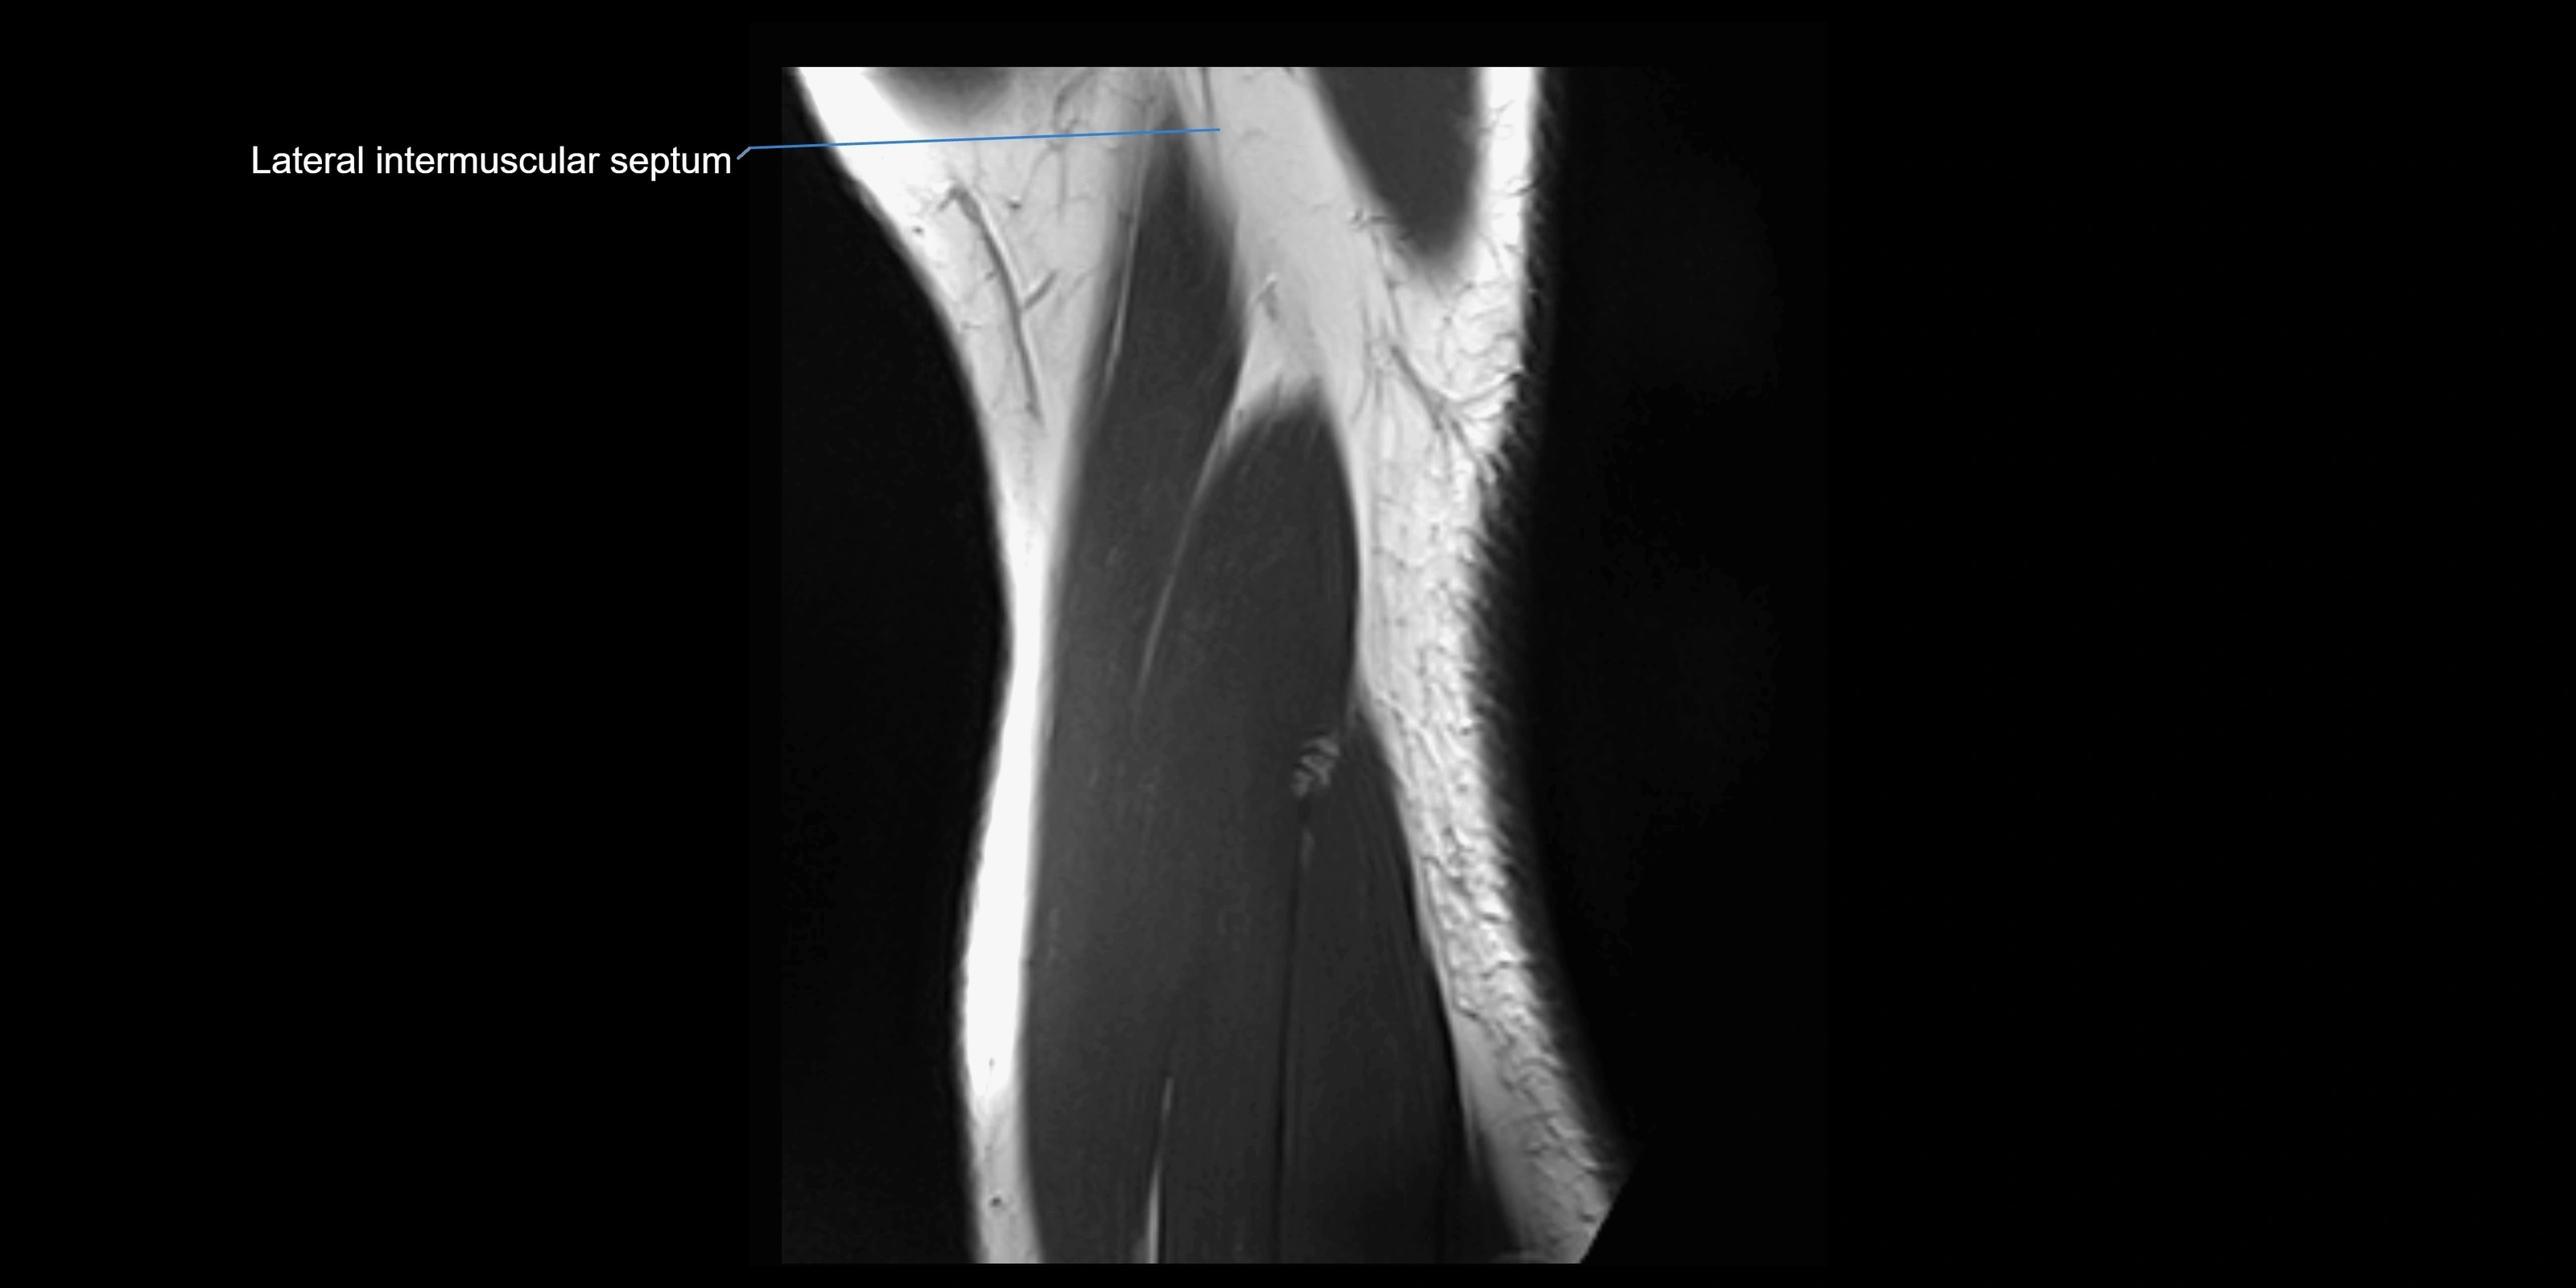

MRI images

image